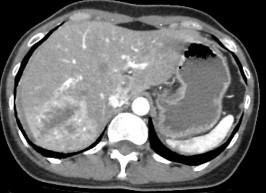

Hình 4.2: CTG độ III. Tụ máu dưới bao 7mm. Phân thùy sau có đường vỡ kèm tụ máu trong nhu mô gan kích thước 49 x 58mm, xung quanh có rối loạn tưới máu nhu mô.

Nguồn: BN Nguyễn Thị T, 60t HS: 2113618